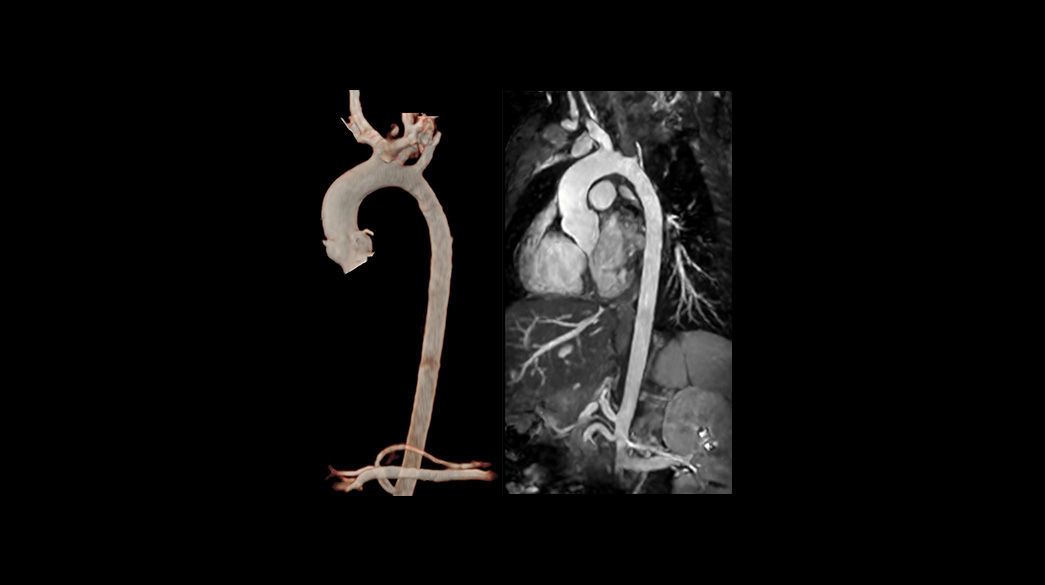

Inhance-Suite1040-x-585

ViosWorks1040-x-585